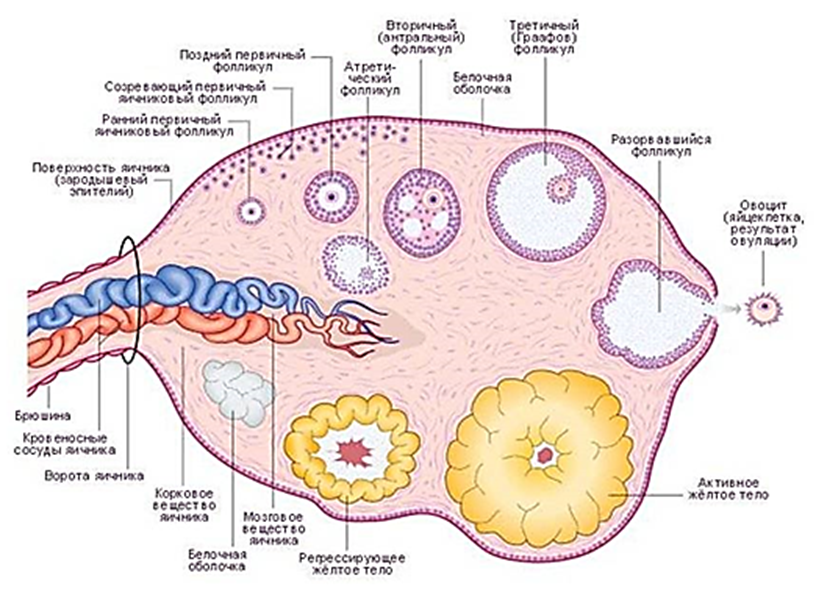

Созревание фолликула в яичнике: этапы и процессы